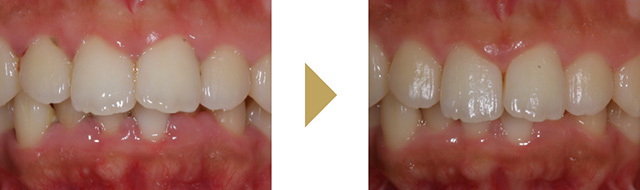

歯周病の程度がそれほどひどくなければ、上手な衛生士さんの治療で歯周病は治ります。ただ歯周病の状態が重度であればこれだけではなかなか治りません。次の治療のステップは歯周外科治療です。

麻酔をして少し歯茎を開いてあげると、歯周病菌を目で見て除去することが可能になり、徹底的に歯周病菌を除去できます。また格段に歯周病治療の成績が向上します。条件が揃えば、失ってしまった骨を増やすような再生治療を行うことも可能です。